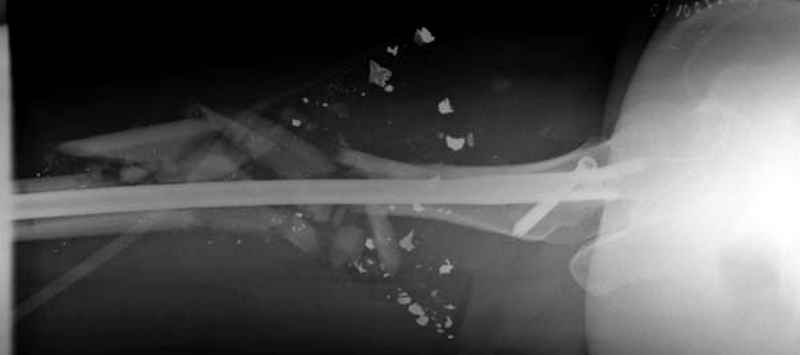

3 такие раны после удаления пули и остатков одежды можно закрыть первично